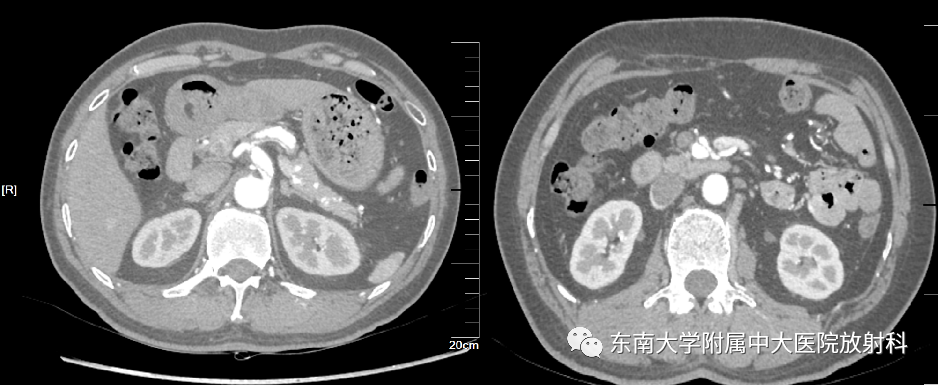

病例

男,44岁

主诉:腹痛一天

现病史:患者1天前无明显诱因下突发腹痛,位于脐周,阵发性,无畏寒发热,有腹胀、有恶心无呕吐,未排便

既往史:高血压病10余年,最高150/90mmHg